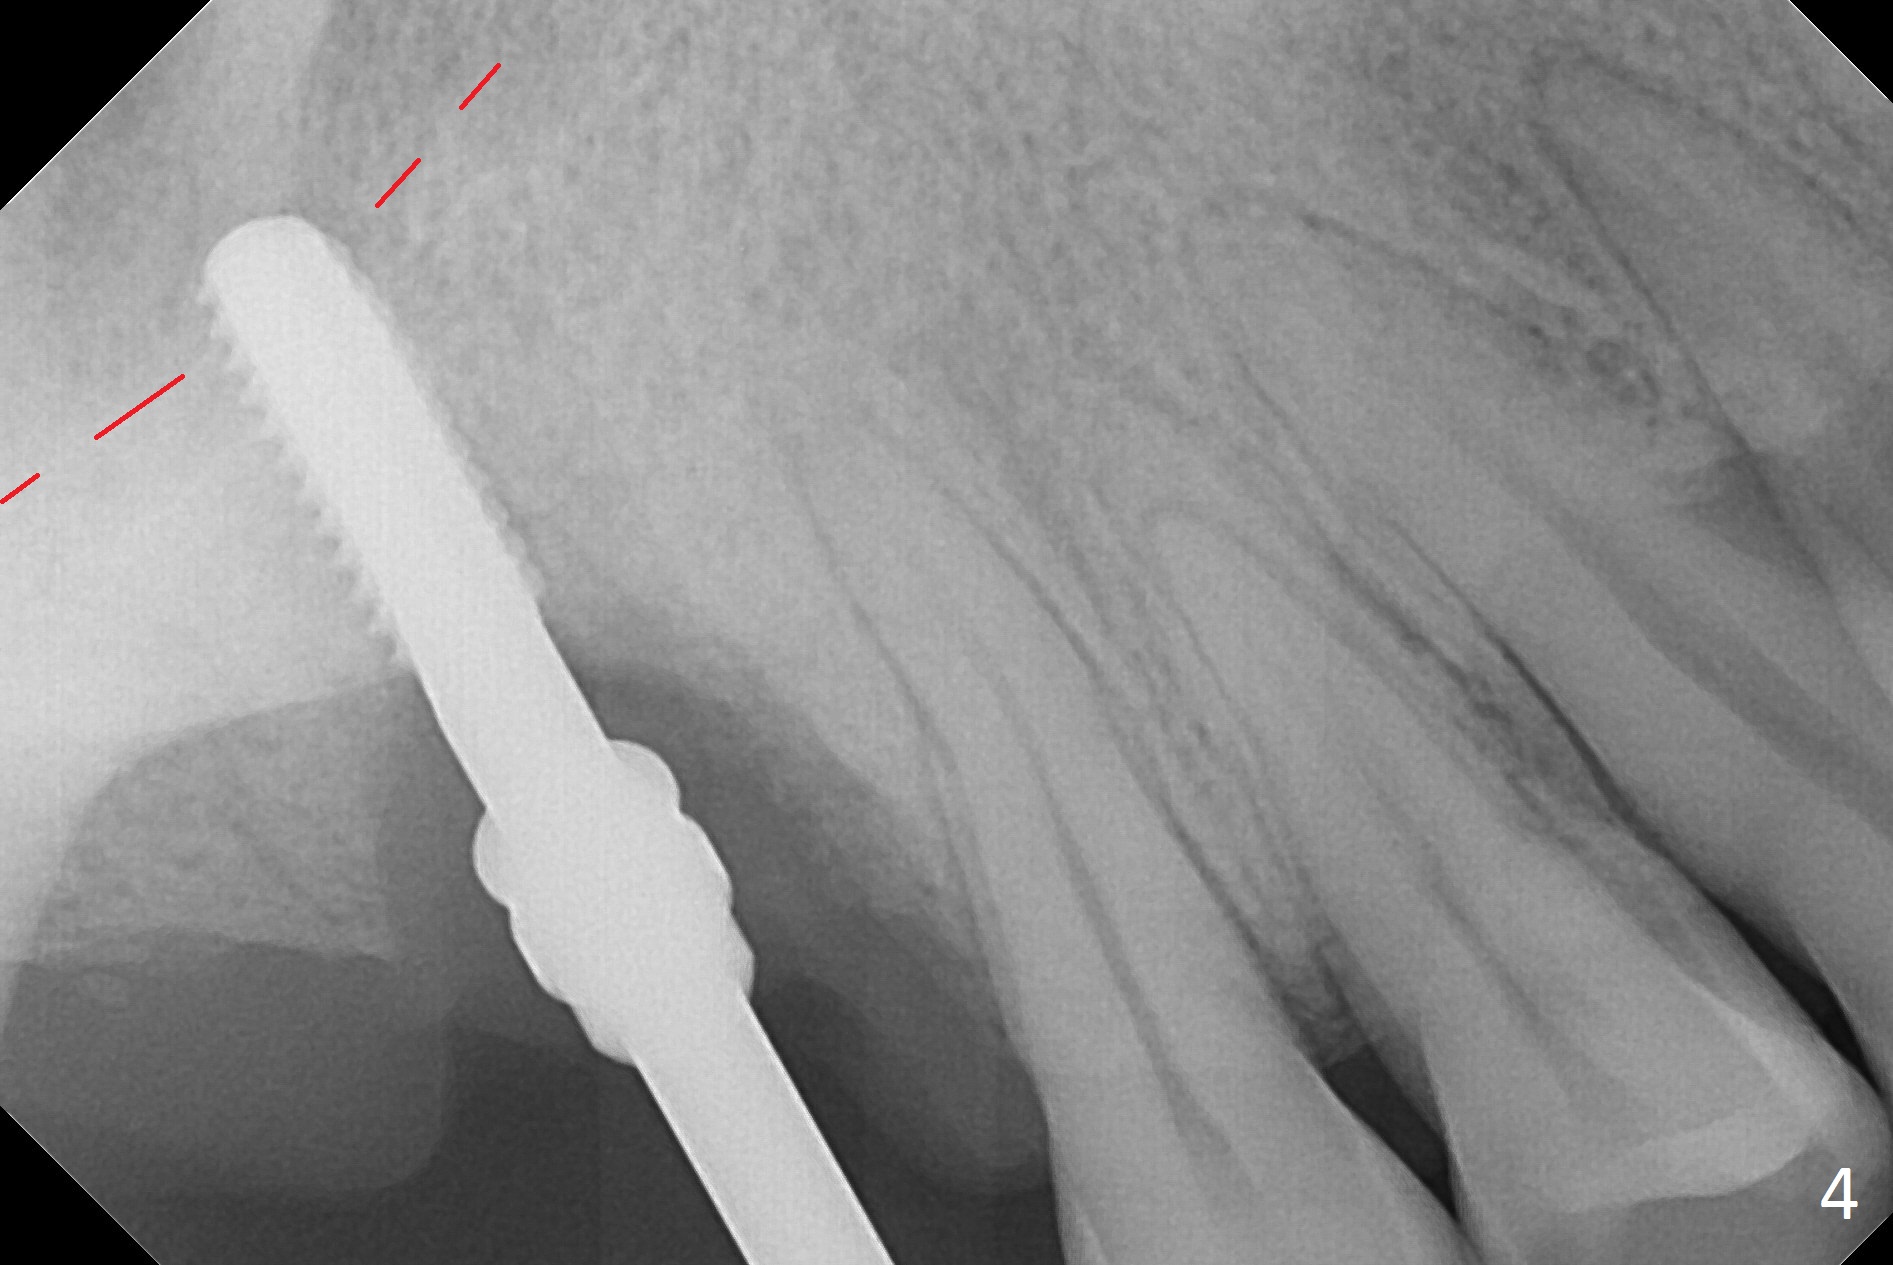

The palatal socket (Fig.1 P, packed with gauze) is intact, but implant trajectory may not be ideal. Buccal to the palatal socket are 2 pieces of the gingiva, buccal (B) and Septal (S). After the septal gingiva is pushed buccally (Fig.2 arrow), the underlying sloped septal bone is exposed (Fig.3 white area). Osteotomy is established as palatal as possible (Fig3 black circle) using DIO Sinus Master Kit, supplemented by Tatum osteotomes and DIO SM 3.8 mm tap drill for final sinus lift (Fig.4). Following further osteotomy using 4.1 and 4.5 mm taps, a 4.5x10 mm implant (Fig.6,7) with insertion torque >65 Ncm. Due to buccal bone loss, the coronal buccal threads are exposed 1-2 mm, which is covered by combination of allograft, autogenous bone and Osteogen. Prior to implantation, PRF plug and bone graft are used for sinus lift. The septal gingiva now is approximately 1-2 mm coronal to the implant plateau (Fig.5 S). The most coronal buccal gingival defect is covered by 3 pieces of PRF membrane (Fig.5 M) against a 6.8x5.5(6) mm abutment (A). Finally the socket is protected by periodontal dressing (Fig.8).